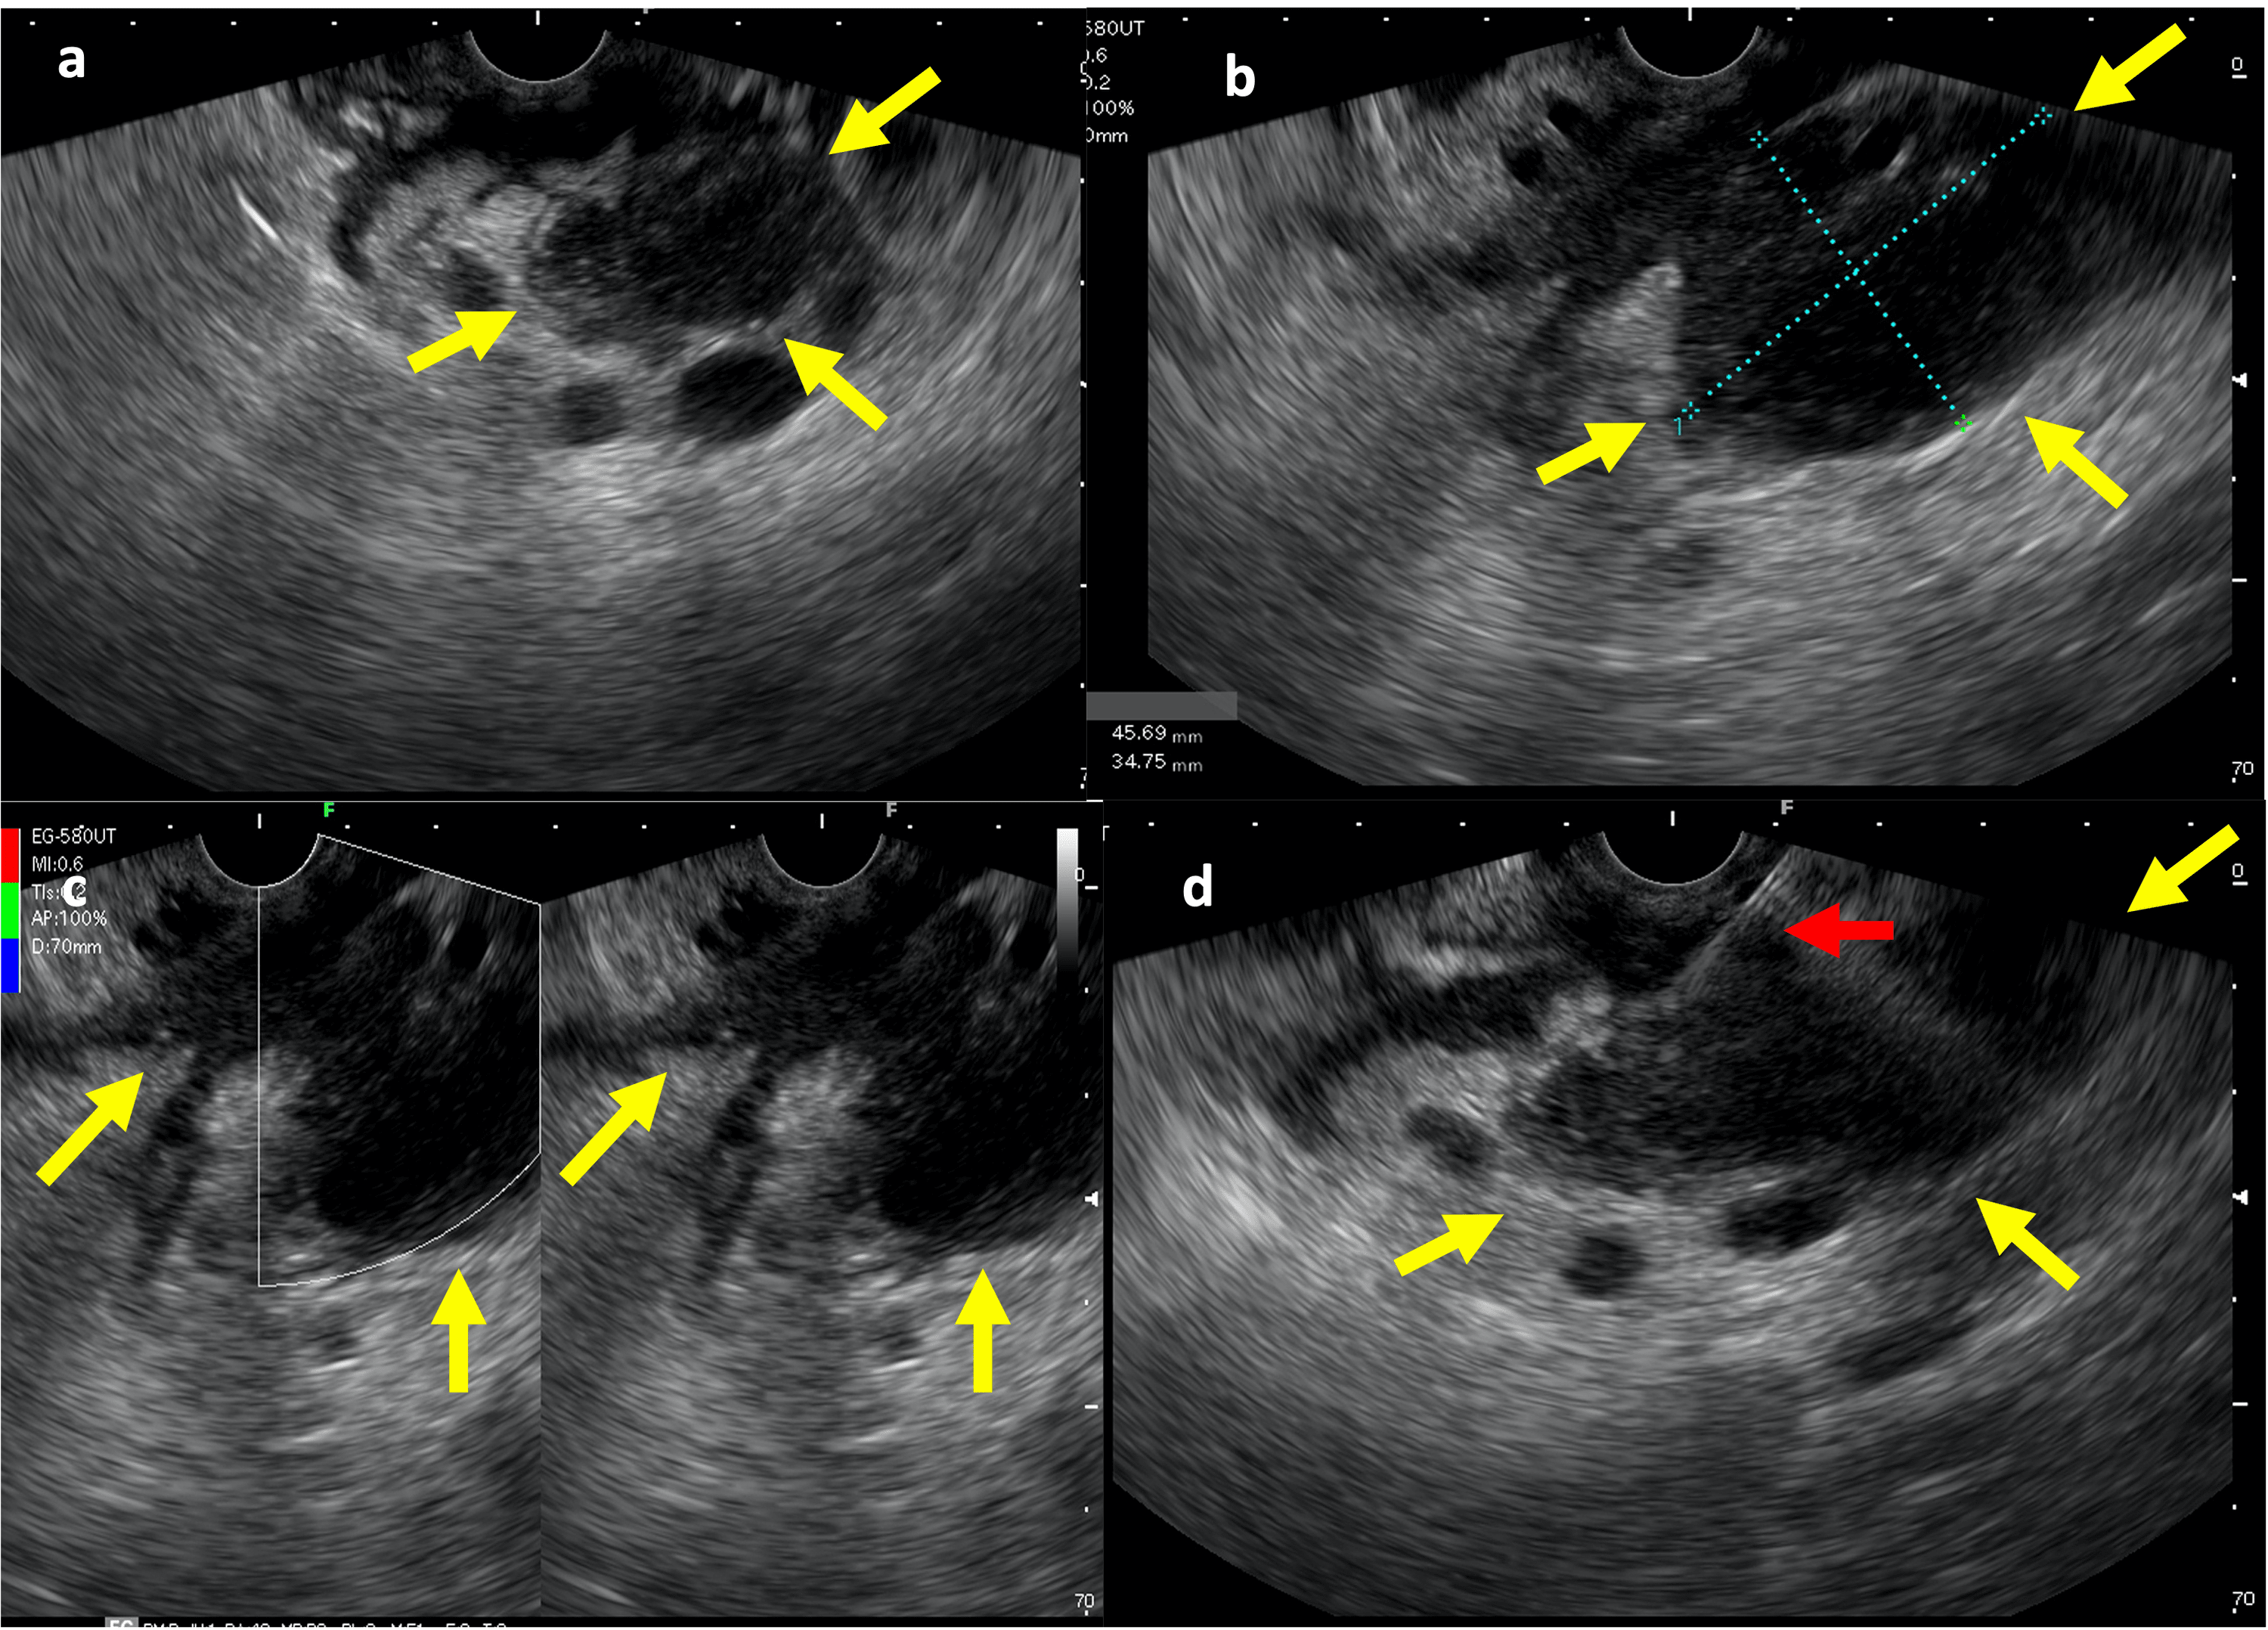

Endoscopic ultrasound pictures of radiofrequency ablation of pancreatic Endoscopic Ultrasound Pancreas Side Effects What are possible side effects? the advancement in the radiological imaging and interventional endoscopy (including endoscopic. how should patients prepare for an eus? an endoscopic ultrasound (eus) procedure examines the inside of your digestive tract. Eus can be used to. Endoscopic ultrasound (eus) is an important technology with many established applications that. What happens after an eus?. Endoscopic Ultrasound Pancreas Side Effects.

From www.researchgate.net